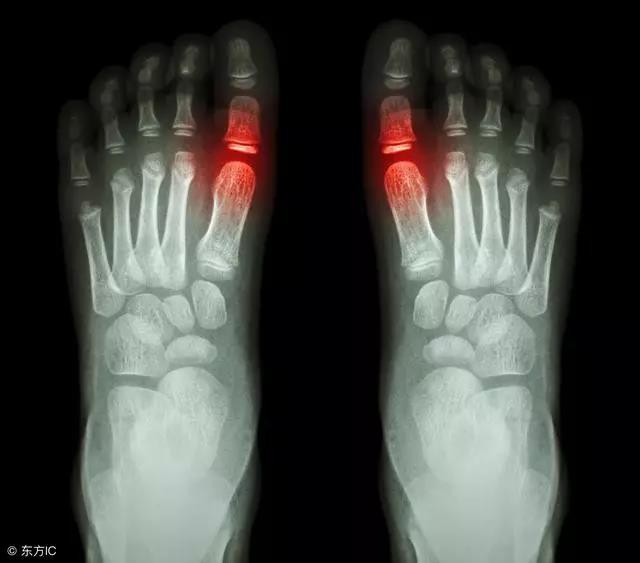

痛風用藥:想減少體內尿酸生成量,該選用非布司他還是別嘌醇?

得了痛風之后,止痛、降尿酸、堿化尿液是治療三部曲。而作為三部曲中最重要的一環降尿酸,目前常用的方法有兩種:一種是通過減少體內尿酸的生成量,一種是增加尿酸的排泄量。

非布司他與別嘌醇是減少尿酸生成量應用最廣泛的兩種藥。不少痛風患者不知道哪種更好,今天,“問上醫”就為您分析對比下這兩種藥。